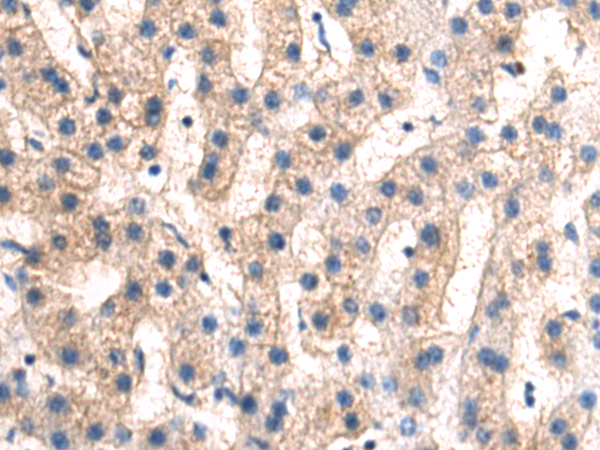

分类: 科研抗体货号: P02366别名: UTY1; KDM6AL应用: IHC反应种属: Human